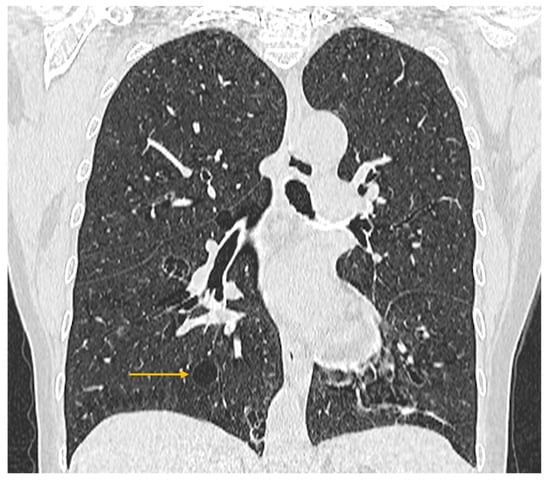

The Role of Imaging Techniques in the Evaluation of Extraglandular Manifestations in Patients with Sjögren’s Syndrome

Sjögren’s syndrome is a chronic autoimmune disease marked by lymphocytic infiltration of the exocrine glands and the development of sicca symptoms, yet some patients also develop extraglandular involvement. Imaging has become relevant for describing these systemic features and supporting clinical assessment. This review discusses the roles of ultrasonography, elastography, computed tomography, and magnetic resonance imaging in evaluating multisystem disease associated with Sjögren’s syndrome. Ultrasonography and elastography help assess muscular involvement by showing changes in echogenicity and stiffness that reflect inflammation and later tissue remodeling. In joints, ultrasound can detect synovitis, tenosynovitis, and early erosive changes, including abnormalities not yet evident on examination. Pulmonary disease, most often with interstitial lung involvement, is best evaluated with high-resolution computed tomography, which remains the most reliable imaging modality for distinguishing interstitial patterns. Magnetic resonance imaging is valuable in assessing neurological complications. It can reveal ischemic and demyelinating lesions, neuromyelitis optica spectrum features, or pseudotumoral appearances. Imaging is also essential for detecting lymphoproliferative complications, for which ultrasound and magnetic resonance imaging can reveal characteristic structural and diffusion-weighted imaging findings. When combined with clinical and laboratory information, these imaging methods improve early recognition of systemic involvement and support accurate monitoring of disease progression in Sjögren’s syndrome. Full article